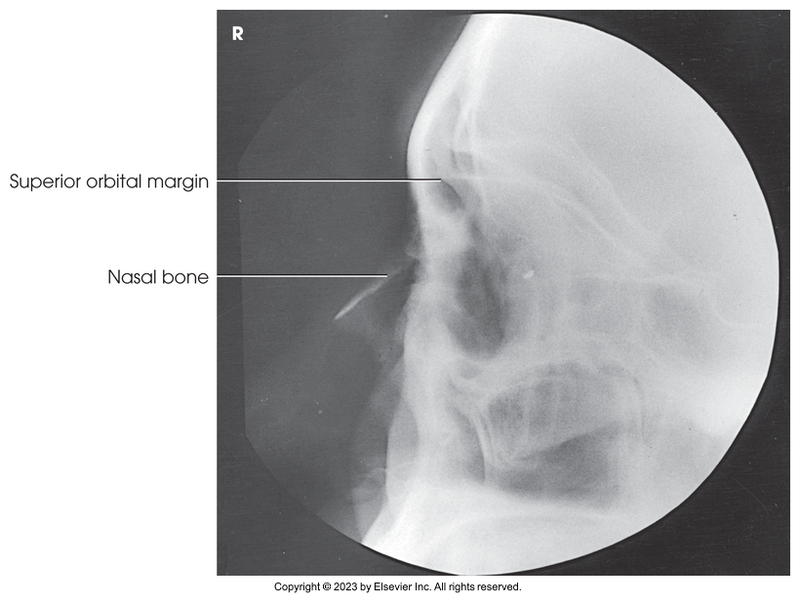

Lateral of facial bones

Lateral Projection of the nasal bones

Lateral facial bones

Lateral of nasal bones